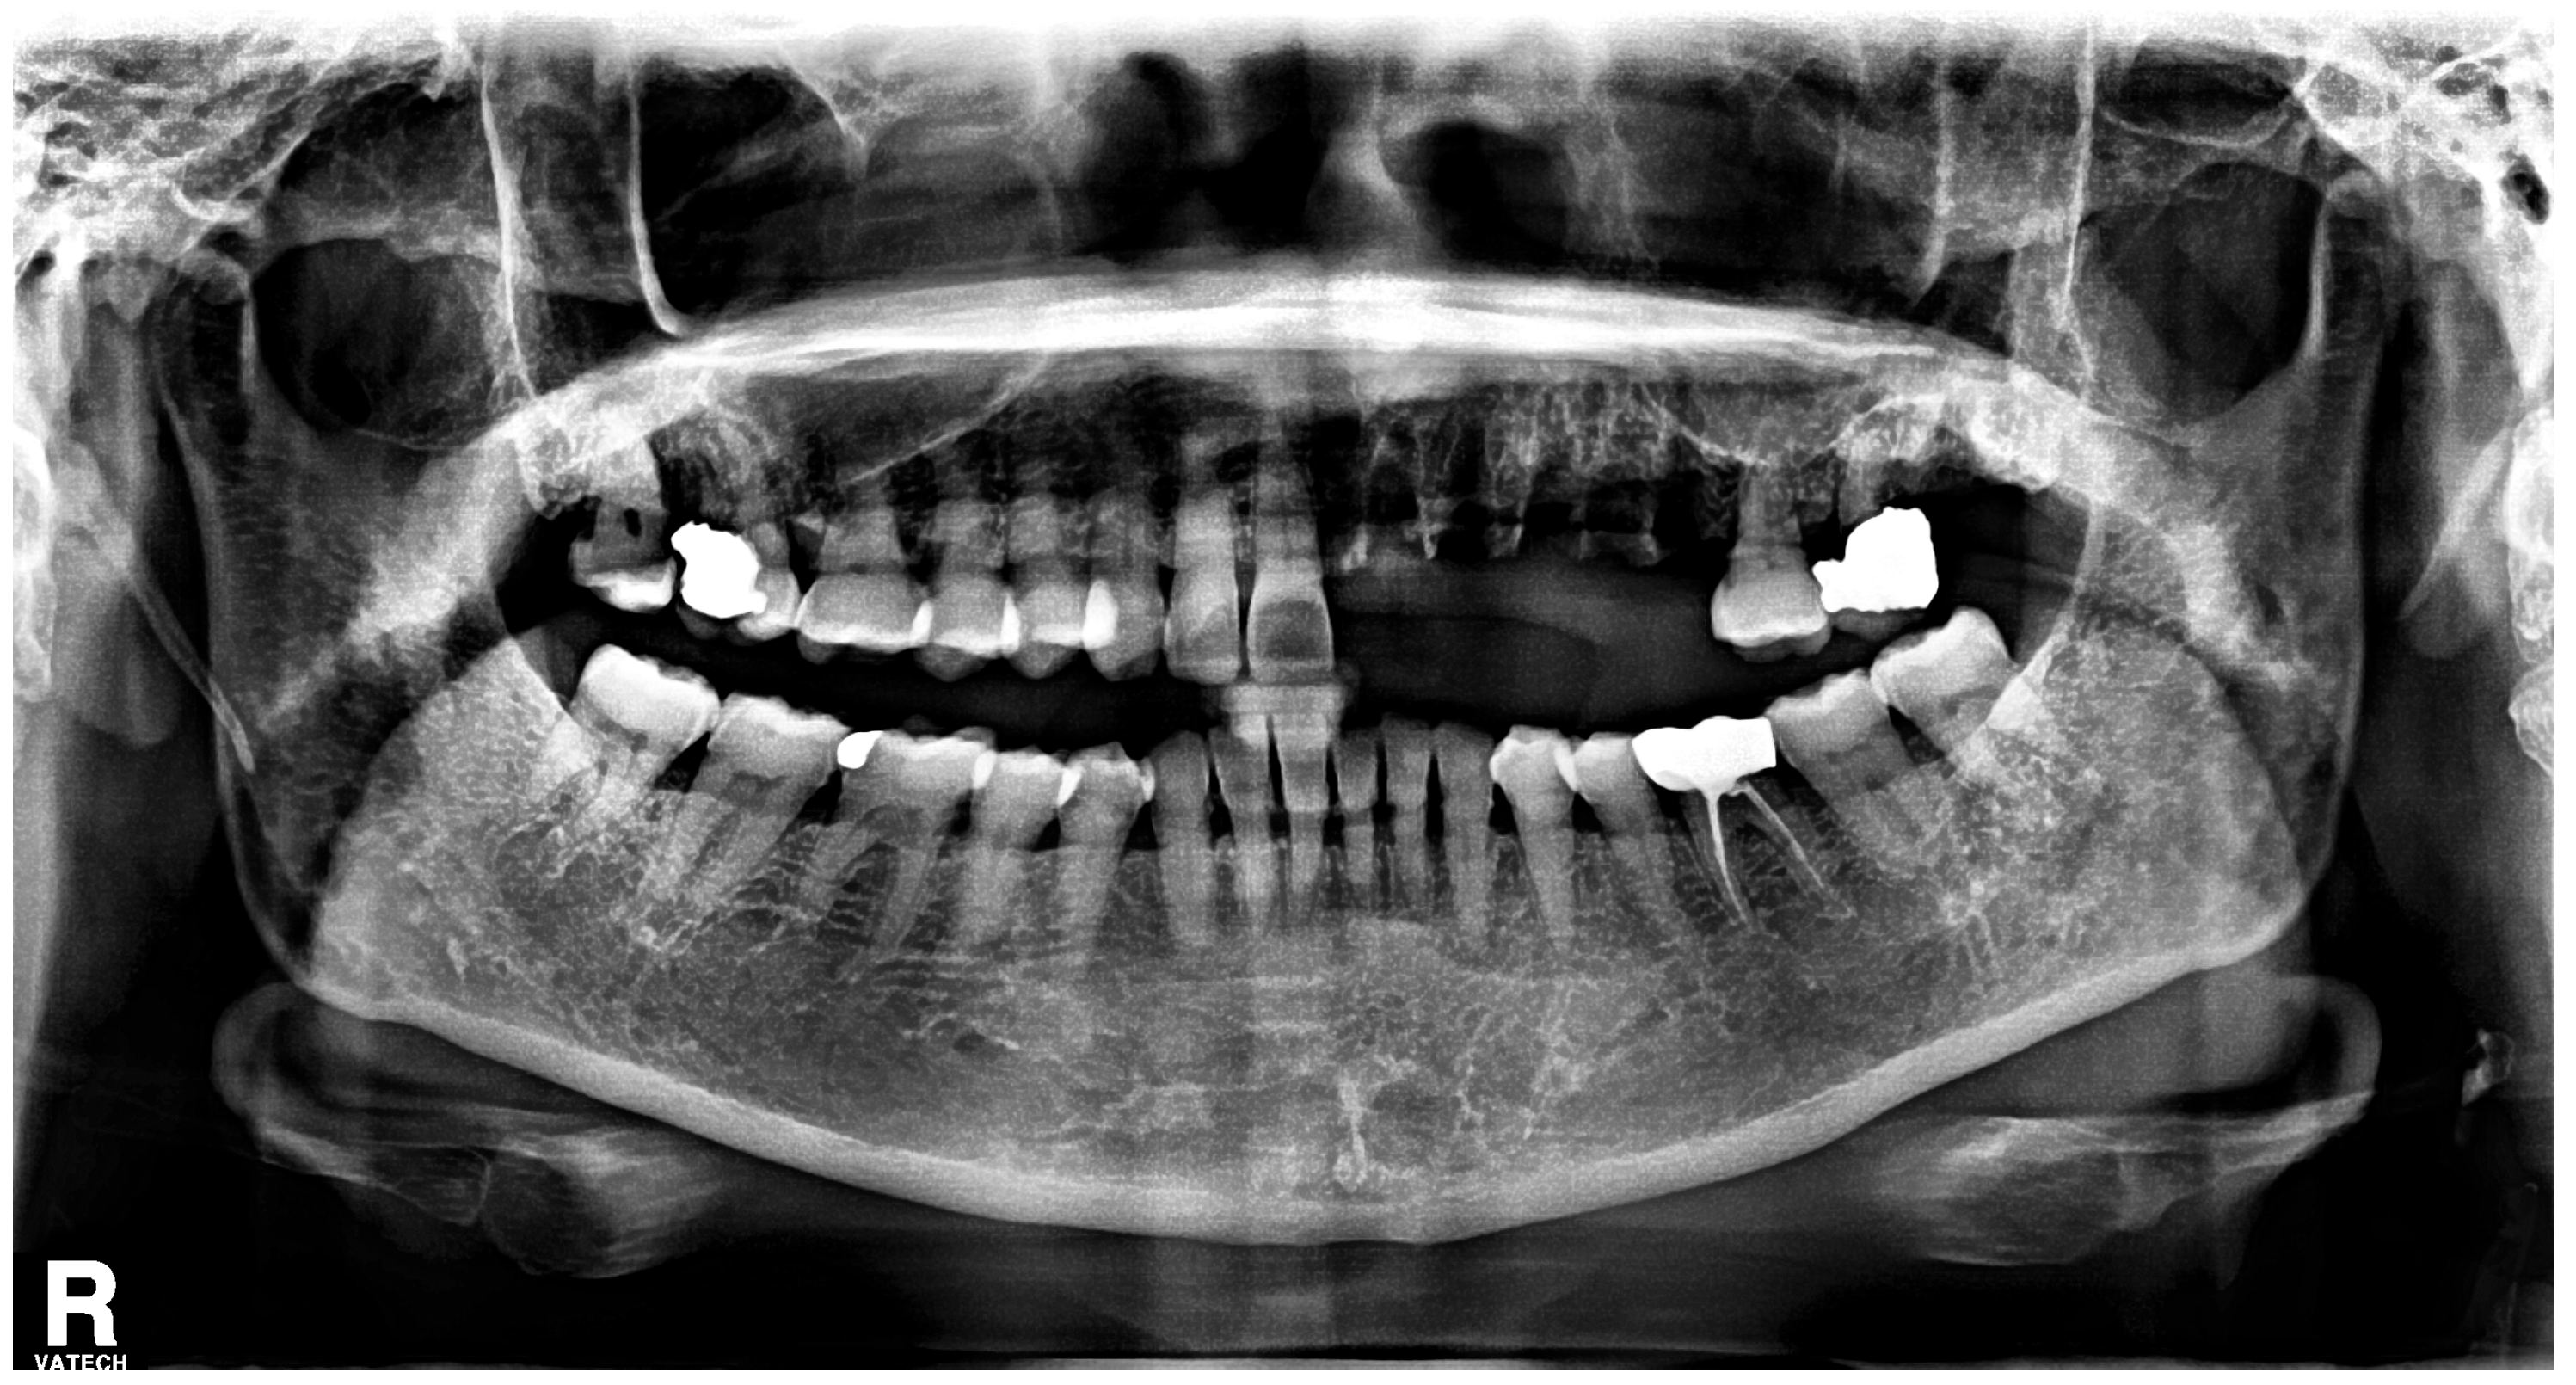

2. Case Report